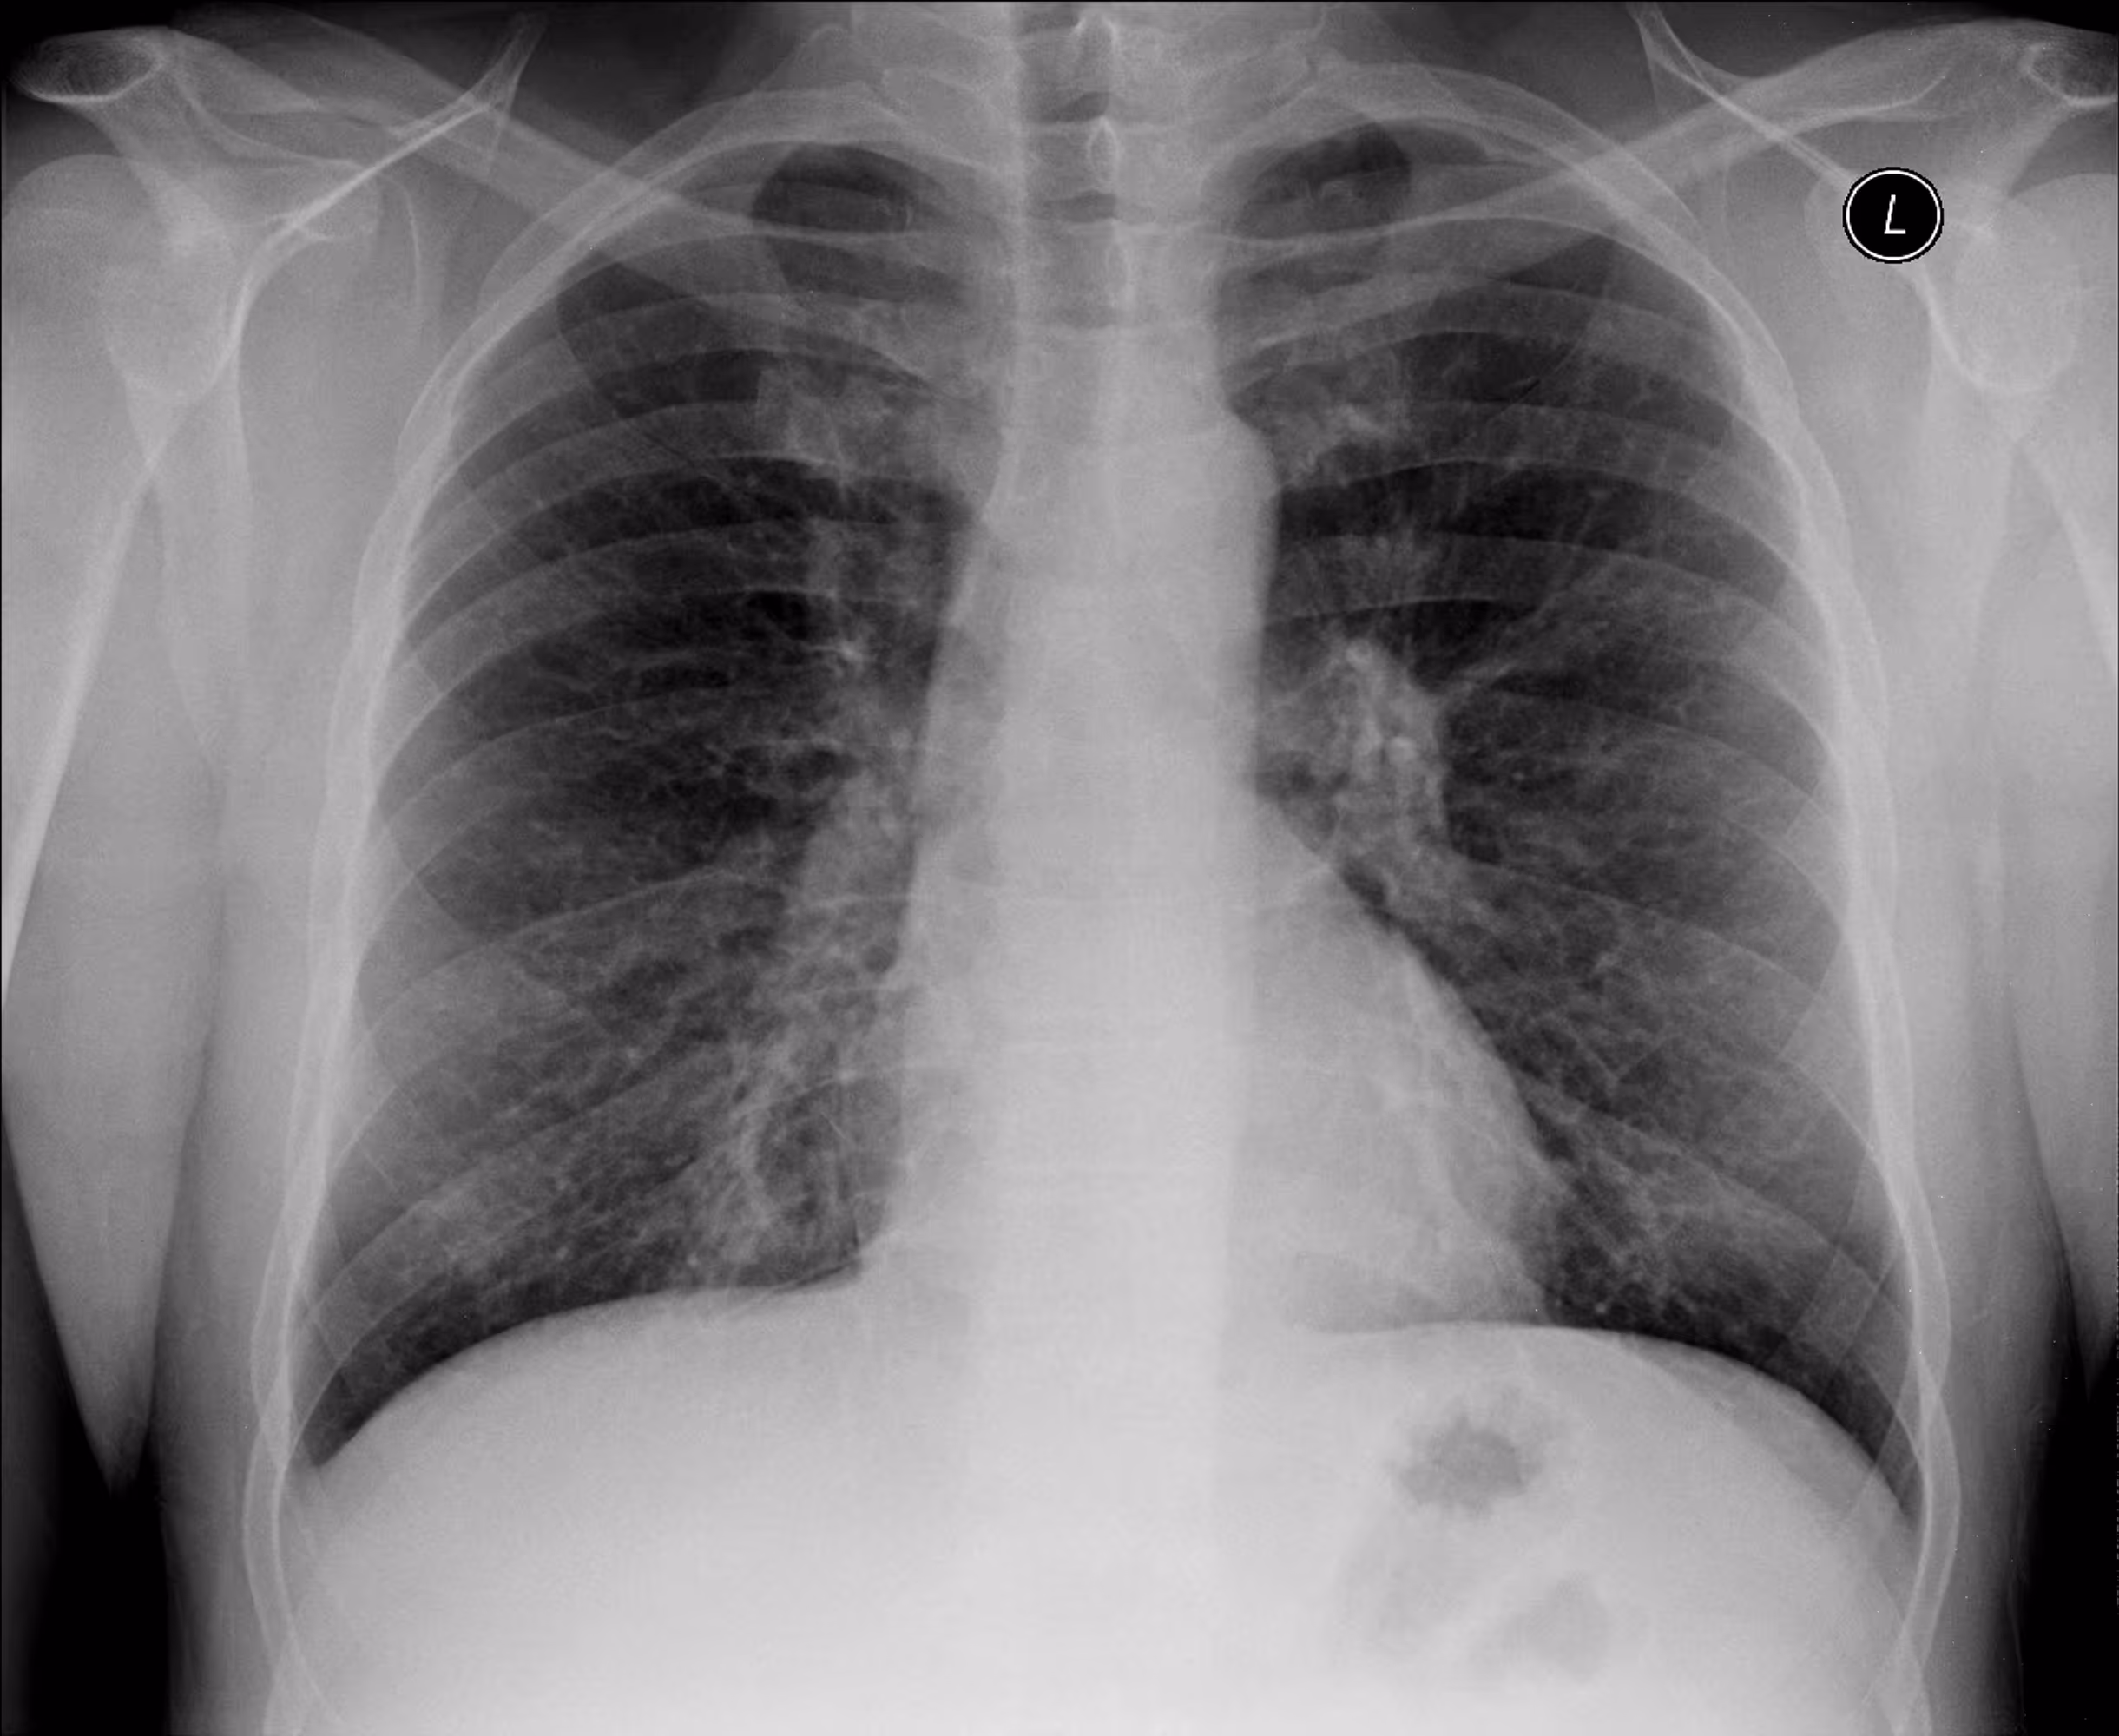

Indication

A 54-year-old male with respiratory difficulty.

Results

ChestView detected an infectious region in the right lower lobe and incidentally identified left hilar lymphadenopathy